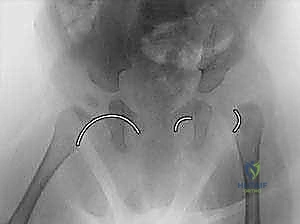

- الأشعة السينية (X-rays): تُستخدم للأطفال الأكبر من 6 أشهر بعد بدء تعظم رأس الفخذ.

صور إضافية لخطوات الجراحة الدقيقة والمتابعة الإشعاعية

يوثق الأستاذ الدكتور محمد هطيف كل خطوة جراحية لضمان أعلى معايير الجودة والشفافية الطبية.